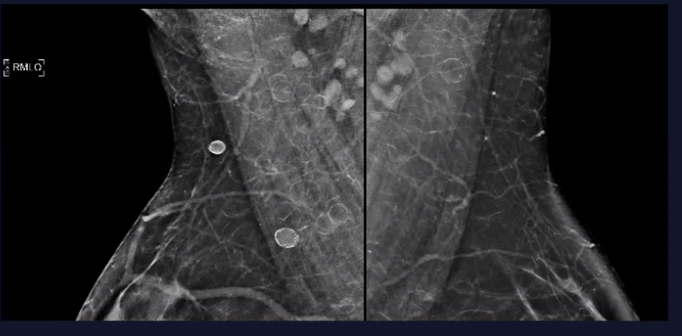

What view is most important when evaluating calcs though to represent milk of calcium?

90 degree lateral view